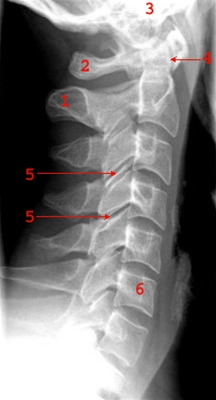

Normalt sidebillede af cervicalcolumna (rygsøjlen, nakke).

1. Processus spinosus

2. Atlas

3. Basis cranii

4. Dens axis

5. Intervertebral led (facetled)

6. Corpus vertebrae C6